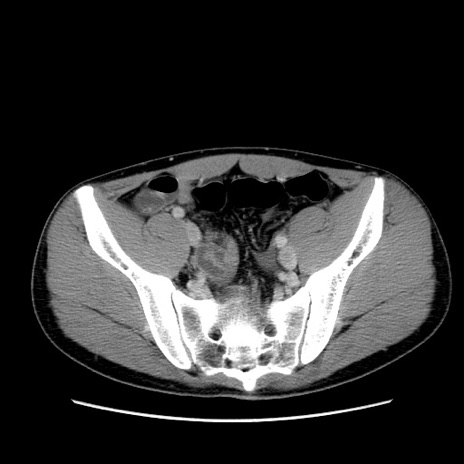

冠状断像

症例36(横断像)

【症例】20歳代 男性

【主訴】心窩部痛

【現病歴】今朝より上腹部痛あり。一旦軽快していたが再度出現したため救急要請。昨日夕に白身の魚を含む刺身を食べた。

【身体所見】BP 136/89mmHg、HR 74/min、BT 37.0℃、腹部:膨満、軟、心窩部に圧痛あり。反跳痛なし、筋性防御なし、腸雑音やや亢進あり。

【データ】WBC 17700、CRP 0.48